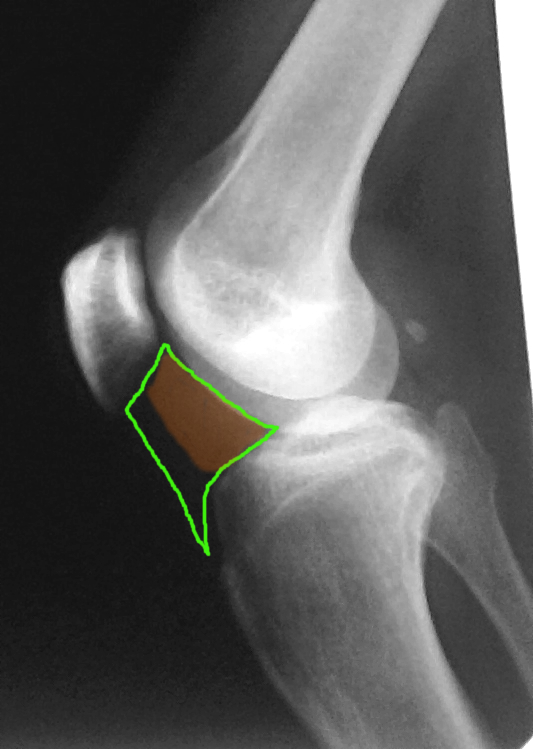

Заболевания и медицинские снимки: Жидкость в коленной чашечке

Раздел: Галерея прозрений